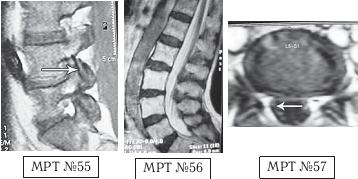

На МРТ № 53 — поясничный отдел позвоночника. На данном «контрольном» снимке, после устранения методом вертеброревитологии секвестрированной грыжи межпозвонкового диска в сегменте LV-SI, наблюдаются остаточные явления дегенеративного процесса. Но в целом состояние поясничного отдела позвоночника, отображённое на этом снимке, довольно хорошее, поэтому будем использовать его для сравнения как вариант нормы.

На МРТ № 54 наблюдается изменение физиологического лордоза, стеноз спинномозгового канала, грыжа межпозвонкового диска и спондилёз в сегменте LIII-LIV, ретроспондилолистез — LIV и LV. Как правило, причина вышеупомянутых болей при таких патологиях скрывается в дугоотростчатых суставах. Дело в том, что при изменении физиологического лордоза извращается «работа» и дугоотростчатых суставов. В состоянии нормы дугоотростчатые суставы имеют дугообразную форму и расположены во фронтальной, горизонтальной и сагиттальной плоскостях в среднем под углом 45о. При развитии дегенеративнодистрофического процесса в межпозвонковом диске (снижении высоты диска, возникновении сегментарной нестабильности) происходит смещение суставных поверхностей дугоотростчатых суставов по отношению друг к другу, что в свою очередь приводит к уплощению физиологического лордоза и его кифозированию (МРТ № 55) или же формированию гиперлордоза (МРТ № 56). И в том, и в другом случае данные процессы, как правило, сопровождаются сдавлением спинномозговых корешков (что вызывает соответствующие боли). Кроме того, сами дугоотростчатые суставы хорошо иннервированы, поэтому протекание патологических процессов, с участием этих суставов, сопровождается соответствующими болевыми ощущениями. ![]() На МРТ № 55 наблюдается уплощение физиологического лордоза в поясничном отделе позвоночника. На МРТ № 56 наблюдается гиперлордоз в поясничном отделе позвоночника. На МРТ № 57 наблюдаются нарушения конгруэнтности в дугоотростчатых суставах в сегменте LV—SI (указано стрелкой) вследствие гиперлордоза. ![]() |